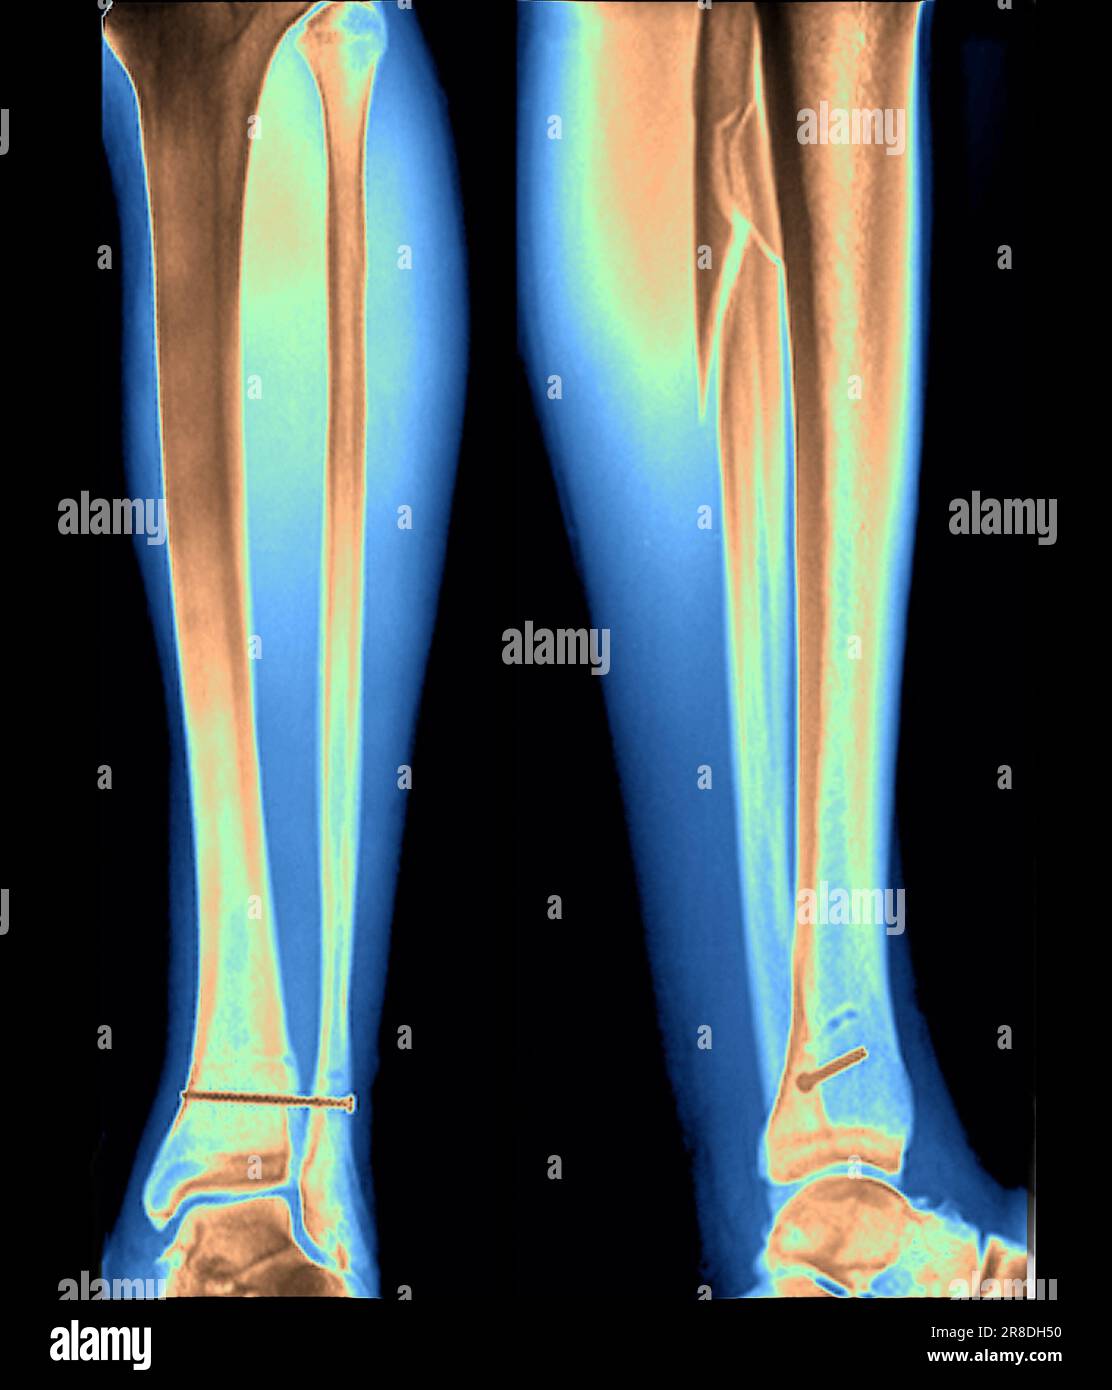

Coloured Xrays of the pinned ankle of a 32 year old male patient. A Calf In Bone Fracture A broken leg (leg fracture) is a break or crack in one of the bones in your leg. Fibula fractures occur around the ankle, knee, and middle of the leg. There are different types of fractures, which can also affect treatment and recovery. If you have a displaced fracture, the care. Common causes include falls, motor vehicle accidents. A broken. Calf In Bone Fracture.

Xrays of the pinned ankle of a 32 year old male patient. A screw is Calf In Bone Fracture What is a broken leg? There are three bones in your leg, including. Healthcare providers also call broken legs fractured legs. Common causes include falls, motor vehicle accidents. Here, health care providers typically evaluate the injury and immobilize the leg with a splint. A broken leg is a bone fracture (broken bone) in your leg. A broken leg (leg fracture). Calf In Bone Fracture.

Xray of the pinned ankle of a 32 year old male patient. A screw is Calf In Bone Fracture What is a broken leg? The proximal tibia is the upper portion of the bone where it widens to help form the knee. Healthcare providers also call broken legs fractured legs. The fibula, or calf bone, is a small bone located on the outside of the leg. A broken leg (leg fracture) is a break or crack in one of. Calf In Bone Fracture.